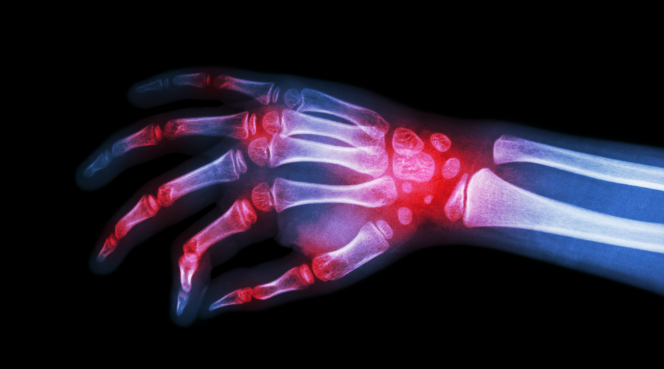

Caracterizada pela perda progressiva da densidade óssea, a osteoporose é uma doença que deixa o paciente mais vulnerável a ocorrência de fraturas.

No paciente com osteoporose, a absorção das células velhas aumenta e a formação de células novas pode diminuir de forma expressiva. Com isso, os ossos ficam mais porosos e menos resistentes, podendo levar a fraturas muitas vezes espontâneas ou causadas por pequenos impactos.

A osteoporose não provoca sintomas. Quando eles surgem, se manifestam pela forma de fraturas sem que tenha havido um trauma expressivo para causá-las, indicando que a doença já está numa fase mais avançada.

A osteoporose não provoca sintomas; quando eles surgem, se manifestam pela forma de fraturas.

O diagnóstico é feito pelo exame de densitometria óssea e o tratamento depende do grau de evolução da doença, podendo envolver uso de medicamentos.